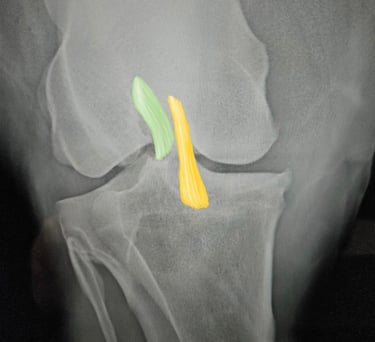

DIAGNOSTICO POR IMAGENES: ECOGRAFIA Y RADIOGRAFIA